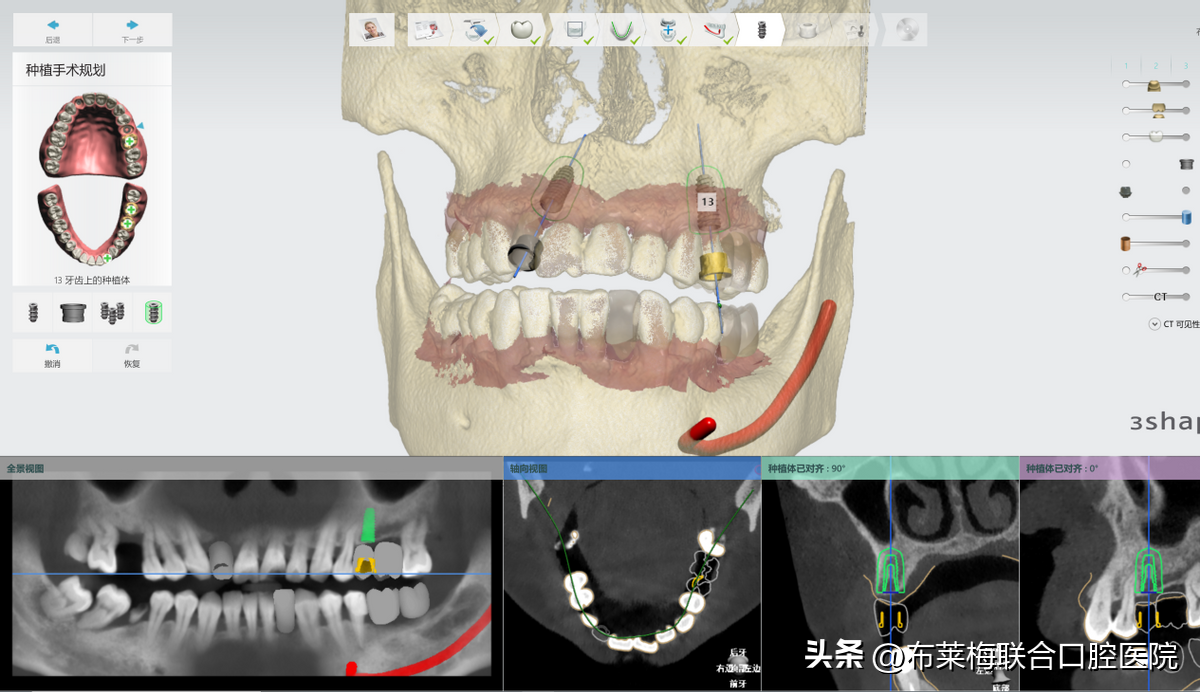

數(shù)字化種植牙技術(shù)可以讓醫(yī)生提前設(shè)計(jì)出調(diào)節(jié)方案,再在計(jì)算機(jī)上模擬生成術(shù)后果圖供患者和家屬確認(rèn)。

真真實(shí)實(shí)的在大屏幕上看到自己的方案,以及種植操作時(shí)的過程,植體走哪里安進(jìn)去,有沒有避開神經(jīng),都是一清二楚。不僅放患者安心,更讓陪同的家屬放心

數(shù)字化種植牙技術(shù)簡(jiǎn)單來說,就是手術(shù)中提前預(yù)判好術(shù)中可能會(huì)出現(xiàn)的風(fēng)險(xiǎn),同時(shí)把誤差減少到毫米,提前讓醫(yī)生和患者知悉確認(rèn)的。降低了手術(shù)的風(fēng)險(xiǎn)系數(shù),也可以讓患者稍微放松心情。恐懼是源于未知,那將這些信息都提前告知患者和家屬,自然對(duì)手術(shù)也就不會(huì)過度緊張

數(shù)字化種植牙利用計(jì)算機(jī)計(jì)算出牙骨組織情況,準(zhǔn)確測(cè)量種牙的位置、角度、深度,做到量體裁衣